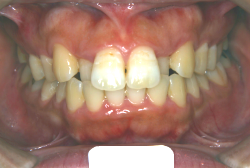

初診時の状態ですが、前歯の噛み合わせが逆転していて、下の前歯が外側に来て、上の前歯が裏側になっています。口元の様子ですが、前歯の重なり方が逆なので、唇の様子もそれを反映して、下唇が突出しています。反対咬合としてはかなり重症です。

分析してみると歯の傾き方に問題があるだけでなく、顎の骨の大きさと形にも問題があることが分かりました。ただし、骨の問題点が見つかったからと言って、必ずしも外科矯正になるわけではなく、このくらいの症状ですと、通常の矯正でもきれいに治すことができます。

診断の結果、下の前歯を正しい位置まで内側に入れていくためには、十分な隙間を確保することが避けられないと判断し、上の左右第二小臼歯と下の左右第一小臼歯は抜歯させて頂くことにしました。歯の本数は減りましたが、歯科医学的評価も大きく改善しましたし、審美的にも大幅な改善が見られますね。特に口元の様子が全然変わりました。